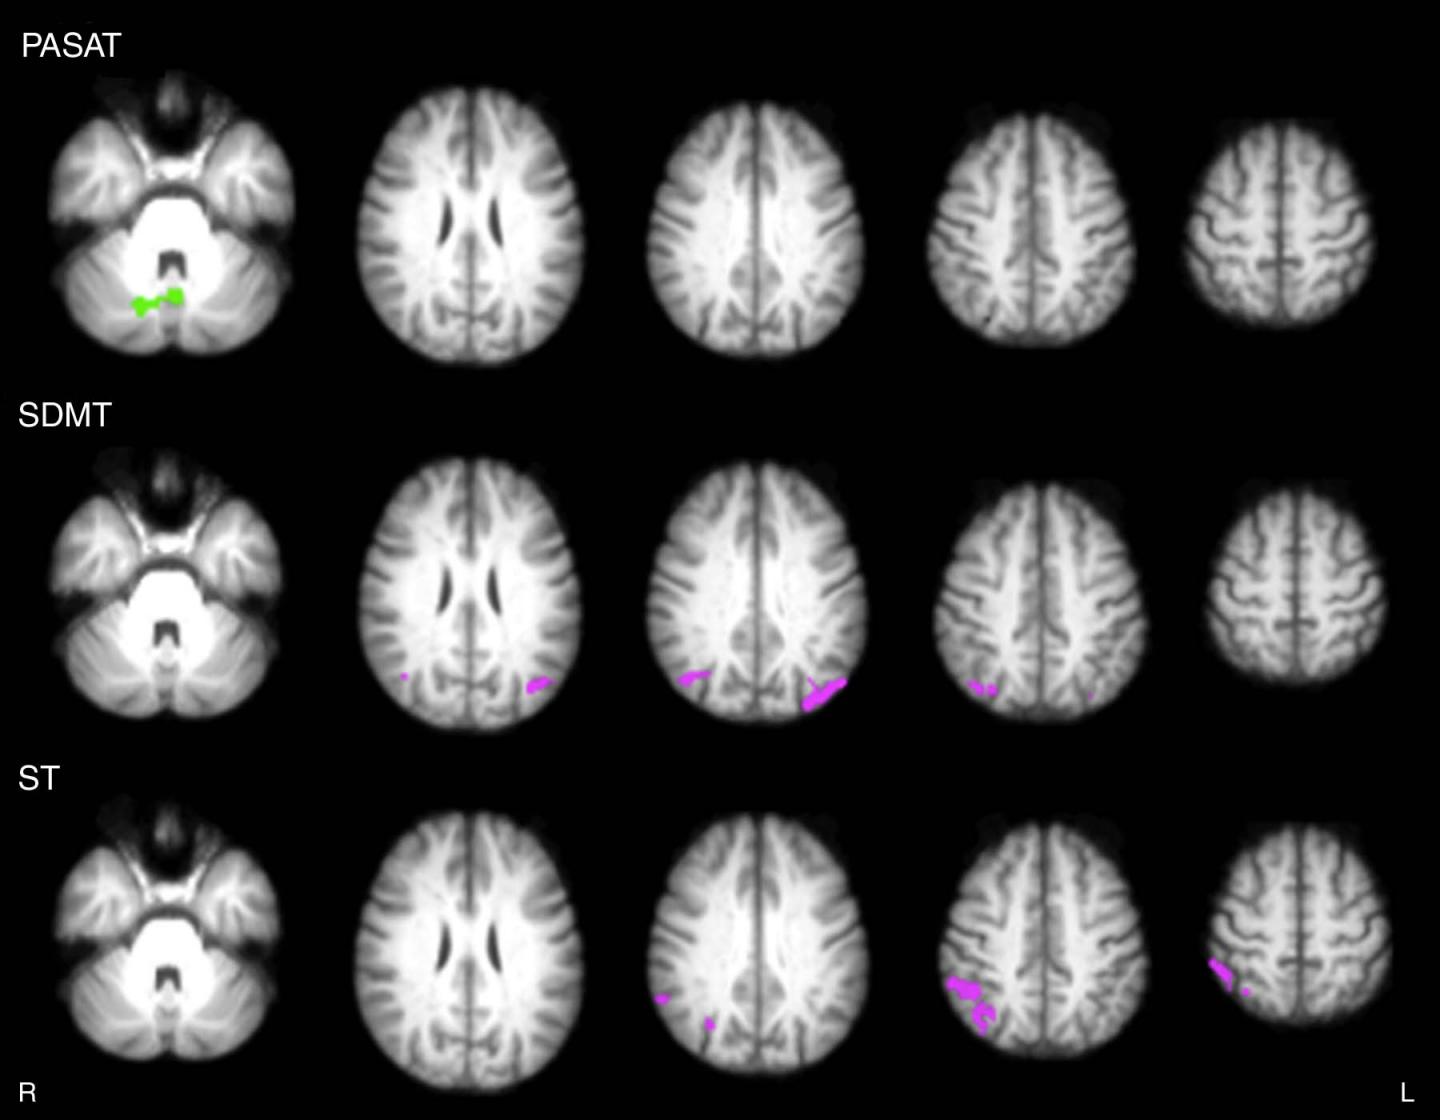

Twenty-four MS patients with cognitive impairment were randomly assigned to either take part in an eight-week, home-based rehabilitation program--consisting of 30-minute gaming sessions, five days per week--or be put on a wait list, serving as the control group. Patients were evaluated by cognitive tests and by 3-Tesla resting state functional MRI (RS-fMRI) at baseline and after the eight-week period. Functional imaging when the brain is in its resting state, or not focused on a particular task, provides important information on neural connectivity.

The modifications in functional connectivity shown in the video game group after training corresponded to significant improvements in test scores assessing sustained attention and executive function, the higher-level cognitive skills that help organize our lives and regulate our behavior.